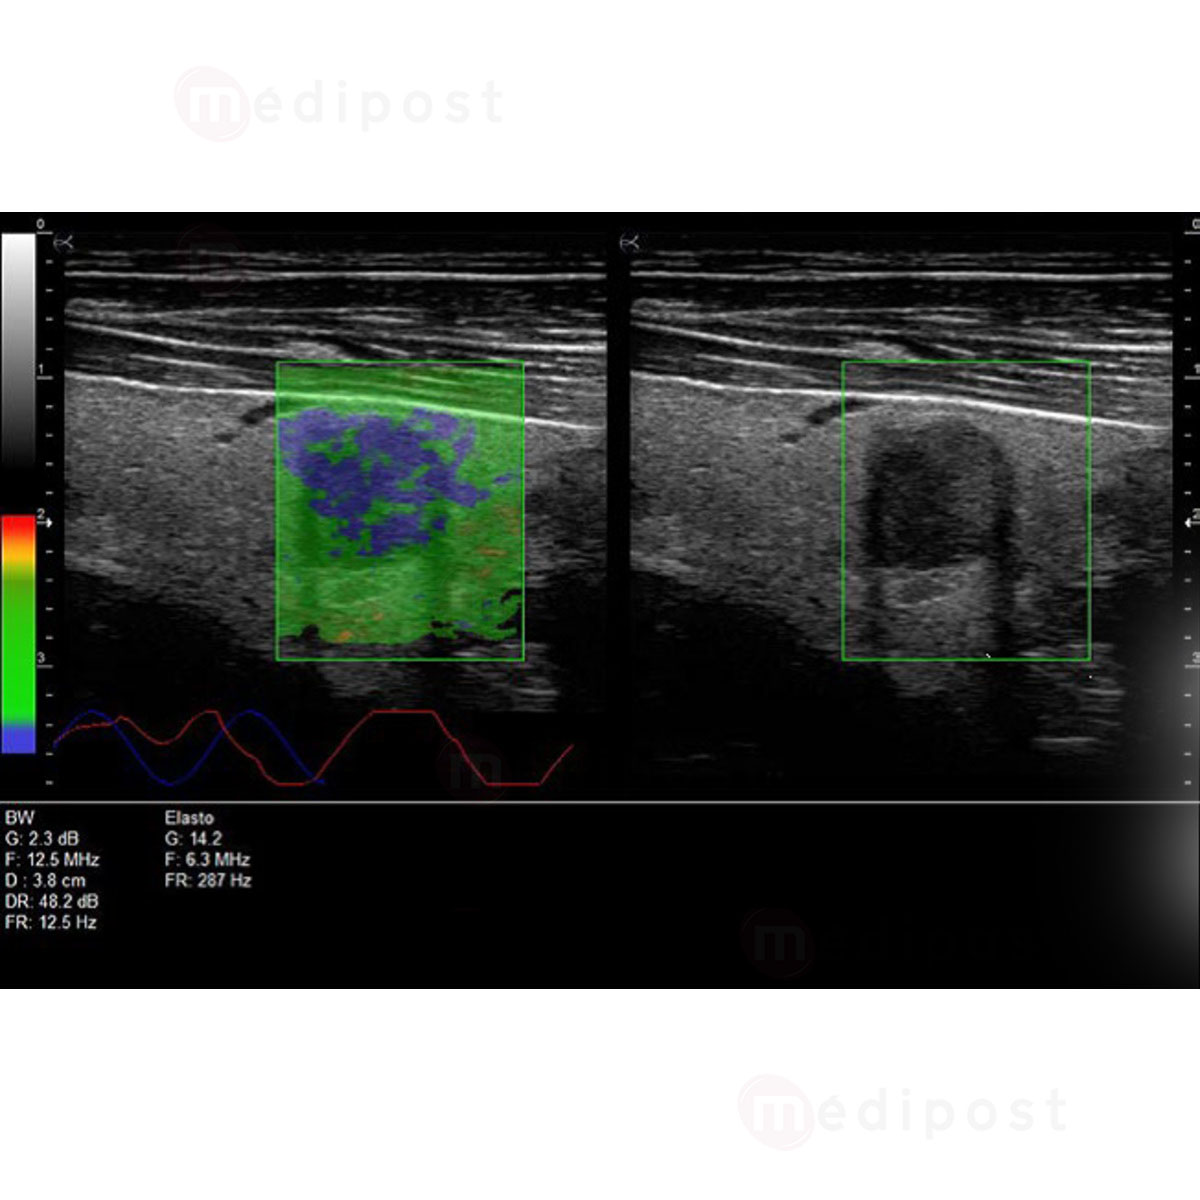

- Options Panoramique et Elastographie

- Elastographie pour une meilleure estimation du risque

- Parties molles

- Sonde Linéaire HD Très haute fréquence 8-18 MHz (Parties molles, Vasculaire, Anesthésie, MSK, Médecine du sport, Pédiatrie)